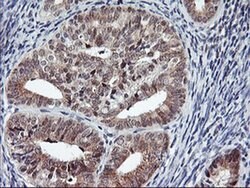

USP10 Mouse anti-Human, Clone: OTI1A10, liquid, TrueMAB™

Ubiquitin is a highly conserved protein that is covalently linked to other proteins to regulate their function and degradation. This gene encodes a member of the ubiquitin-specific protease family of cysteine proteases. The enzyme specifically cleaves ubiquitin from ubiquitin-conjugated protein substrates. The protein is found in the nucleus and cytoplasm. It functions as a co-factor of the DNA-bound androgen receptor complex, and is inhibited by a protein in the Ras-GTPase pathway. The human genome contains several pseudogenes similar to this gene.Specifications

| Flow Cytometry, Immunohistochemistry (Paraffin), Western Blot | |